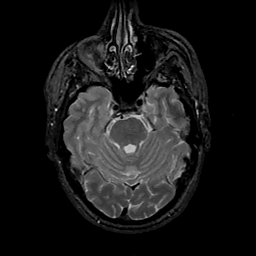

MR Study #11, May 5, 1991 -- Slice #15

[Home][Help][Clinical][Tour 1][Tour 2] Slice 15